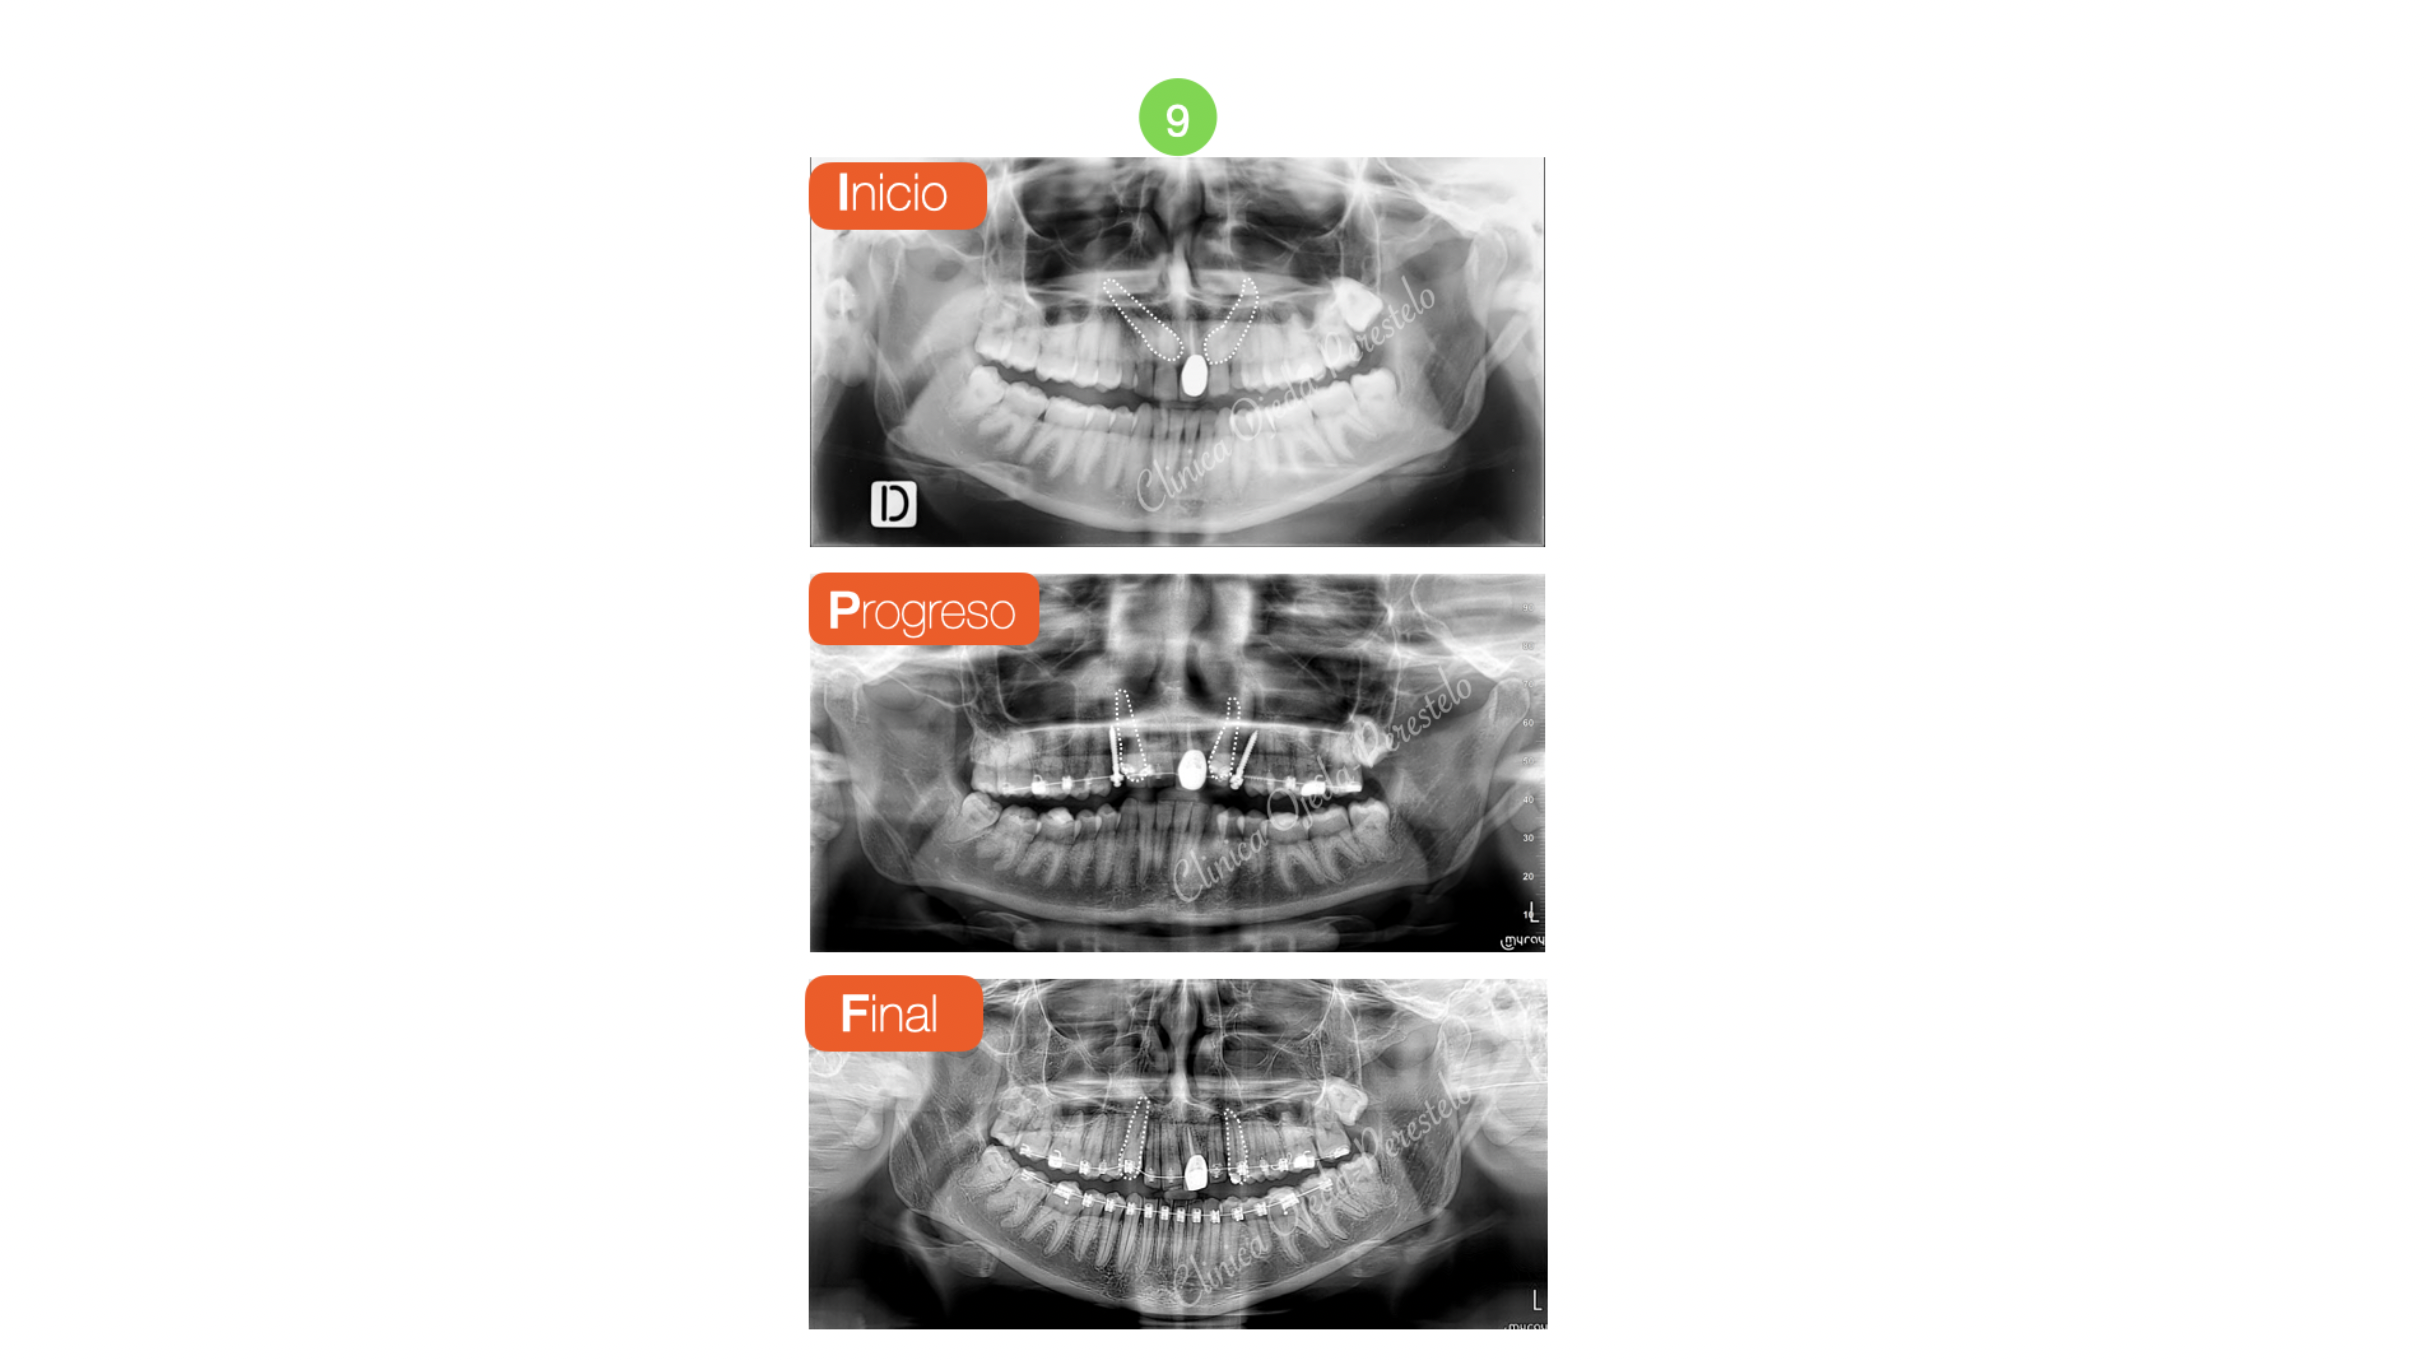

Caninos Maxilares Retenidos (13-23) + Bioestética 21-22

Presentamos a una paciente adulta con los caninos maxilares retenidos y sin posibilidad alguna de erupcionar de manera natural. Su estudio detallado nos confirma  que se encuentran por palatino y con un pronóstico de tracción incierto. Decidimos fenestrarlos e implementar una combinación de vectores distal-extrusivo y vestibular hasta su correcta reubicación dentro de la arcada utilizando como anclaje 2 MT. Este protocolo nos permite proteger de posibles reabsorciones radiculares a los dientes de apoyo.

También hemos ido extruyendo y perfilando la corona sobredimensionada de la pieza 21 hasta dotarle de una proporción adecuada.

Quisiéramos destacar la reubicación y correcta articulación de ambos caninos en la arcada maxilar así como la adecuada colocación del margen gingival de la pieza 21 en relación al 11. Una vez finalizada la Ortodoncia la  paciente se ha realizado un masking dental en la pieza 22 un cambio de corona de la pieza 21. Todo ello le ha dotado de un aspecto más natural a la sonrisa.

Hoy en día los TADs nos han facilitado y simplificado mucho la reubicación de los dientes retenidos y nos han permitido desarrollar estrategias biomecánicas con un mínimo sufrimiento en los dientes adyacentes/apoyo en relación a los procedimientos tradicionales.